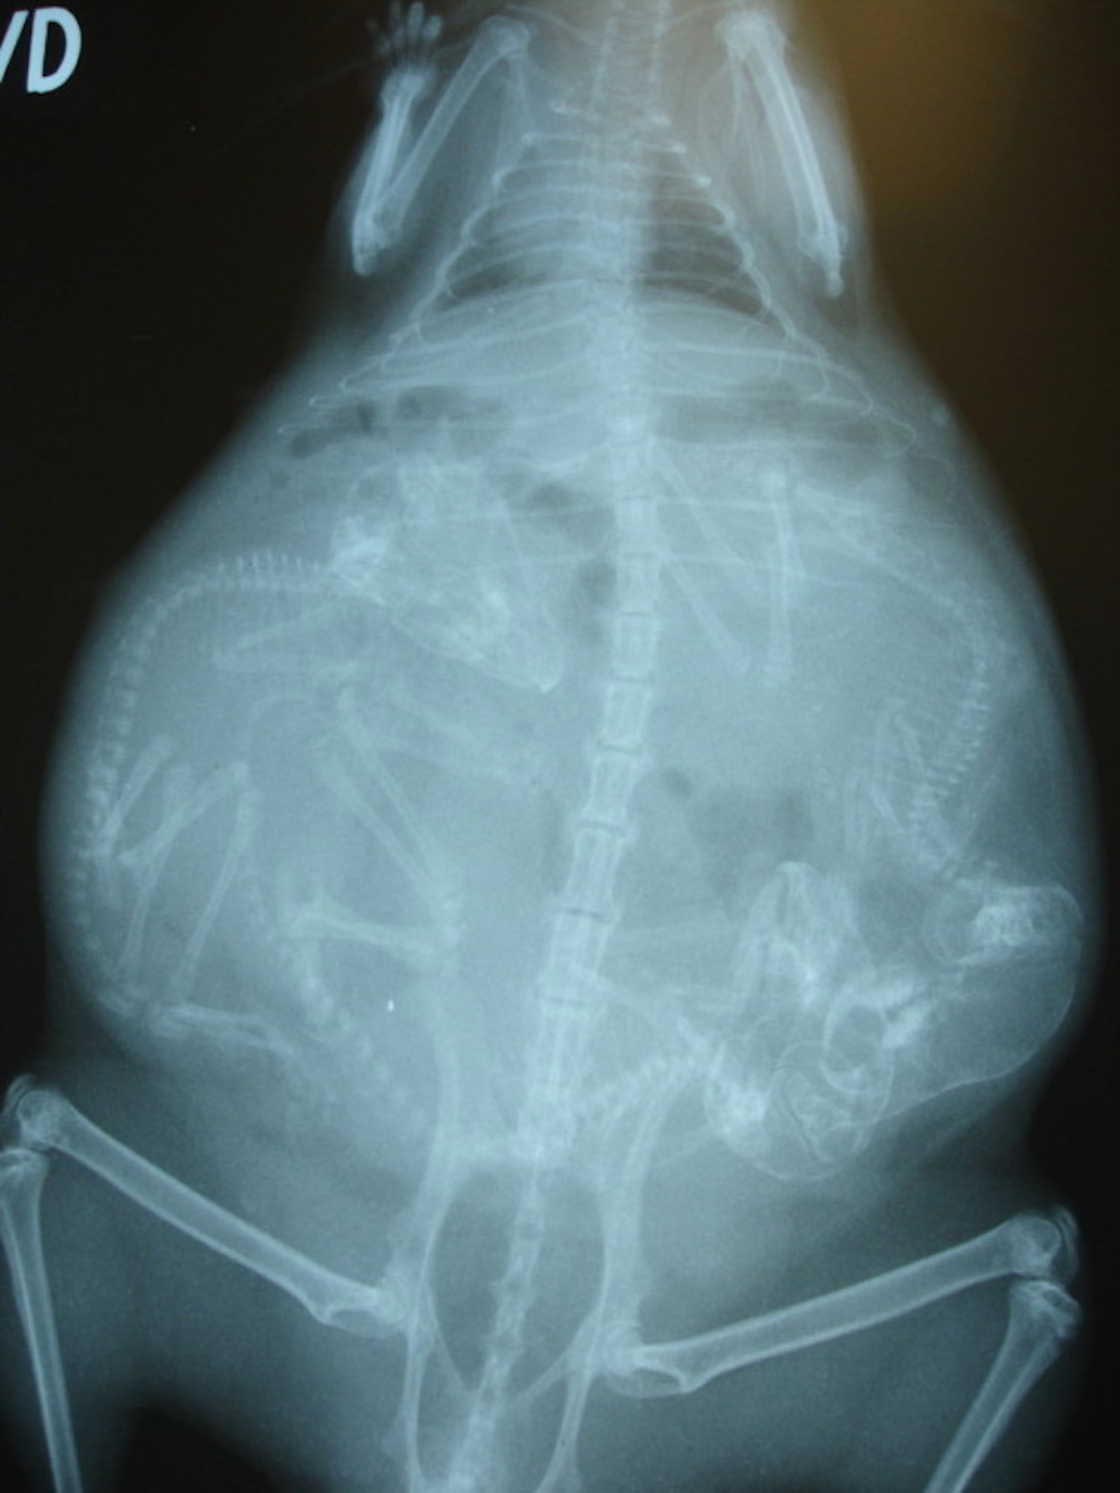

Беременная морская свинка

Самки морских свинок становятся половозрелыми в 2 месяца, но размножение после 8-месячного возраста может быть опасным для детёнышей из-за повышенной жесткости хряща между лобковыми костями у взрослых особей.